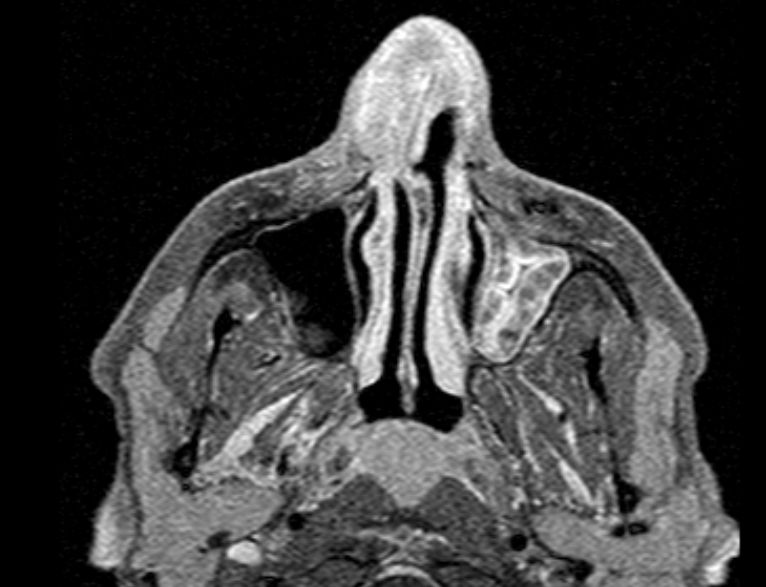

MRT: Plattenepithelkarzinom der linken

Nasenhaupthöhle, R1 reseziert![]() |